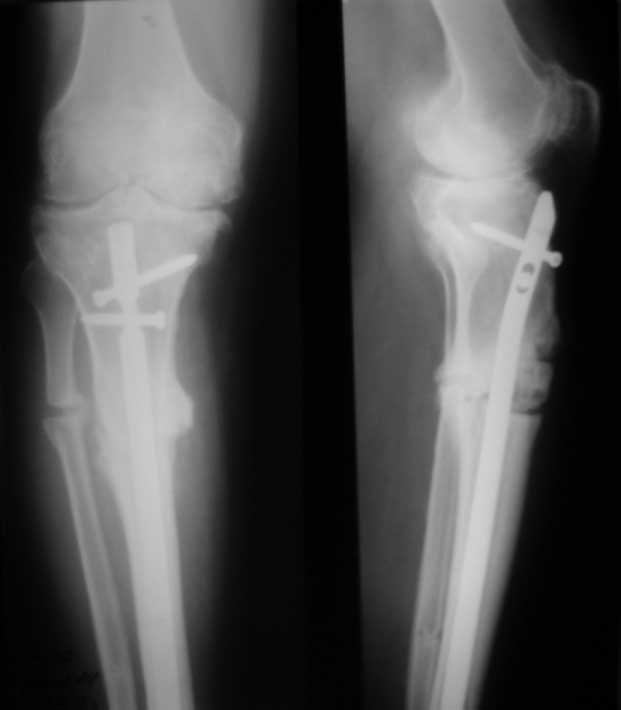

У пациента 50 лет имеется разгибательная контрактура через 8 меспосле ТКА. Уважаемые коллеги. Пациент 8 мес после операции ТКА, в анамнезе – неправильно сросшийся перелом голени, коррекция оси (снимки прилагаются. В настоящее время имеется разгибательная контрактура 10/5/0, на операционном столе было 90/0/5, на момент выписки движения 50/0/0 в надежде на дальнейшую разработку. До эндопротезирования 40/10/0. Глубокая инфекция исключена. Ротация бедренного компонента в норме (по КТ). Вопросы: насколько для такого ограничения критична некорректная установка б/б компонента (я намерял 7 град)? Причина нынешнего состояния, артрофиброз? Какие действия следует предпринять, удаление рубцов, релиз головок 4-главой мышцы? Что-либо другое, ваше мнение? С уважением, Максим Агалаков, Екатеринбург.